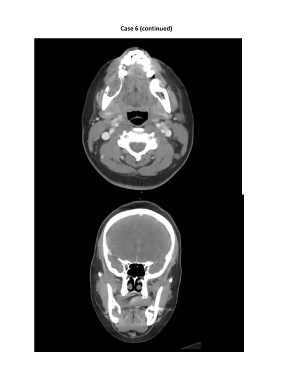

Case 6 (continued)